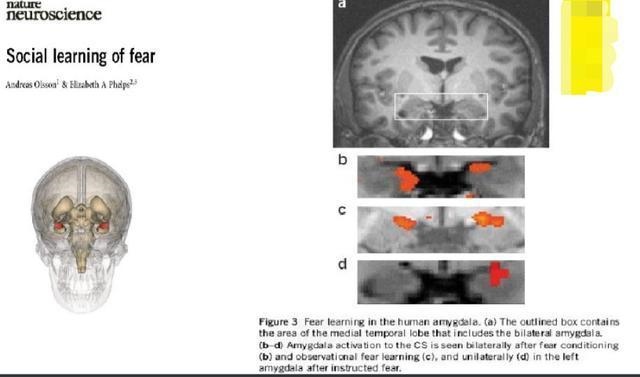

如下这张图,是人类大脑的恐惧中心部位,杏仁核所在的位置,见a图的方框位置。

本实验是请一位学生,在手上戴上放电装置,然后用核磁共振拍其大脑神经元的活化情况,每次一响时,3秒后电就会出来。

b,c,d是不同情况下对应大脑的恐惧中心活化的情况。

b图是只要一响,大脑的恐惧中心立即活化,也就是此时,电还没有出来,但是大脑知道电要来了,于是立即恐惧起来。

c图则是看着被电的人的大脑图,恐惧中心也是活化的,也就是看着别人被惩罚,看的人也一样恐惧。

d图则是电左边的手,大脑右边恐惧中心活化。